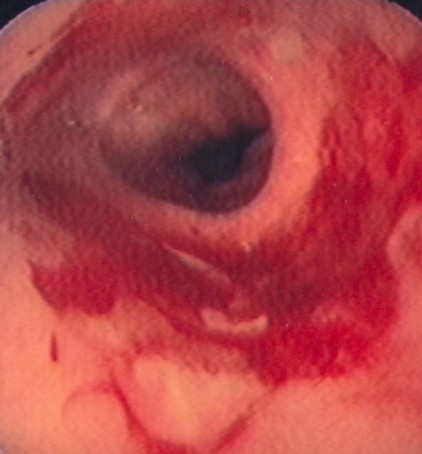

Gastroscopy. Green arrows: orifice of the gastrocolic fistula (Courtesy Dr. V. Penopoulos)